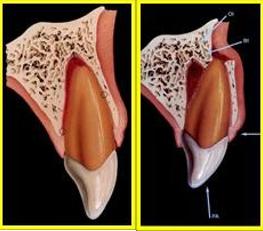

正确应对牙齿外伤的第一步,需要我们判断自己的牙齿损伤的程度。外力撞击可引起牙齿的折断,其中按照折断位置又可分为冠折、冠根折和根折。

A:冠折未露髓;B:冠折露髓;C:冠根折;D:根折